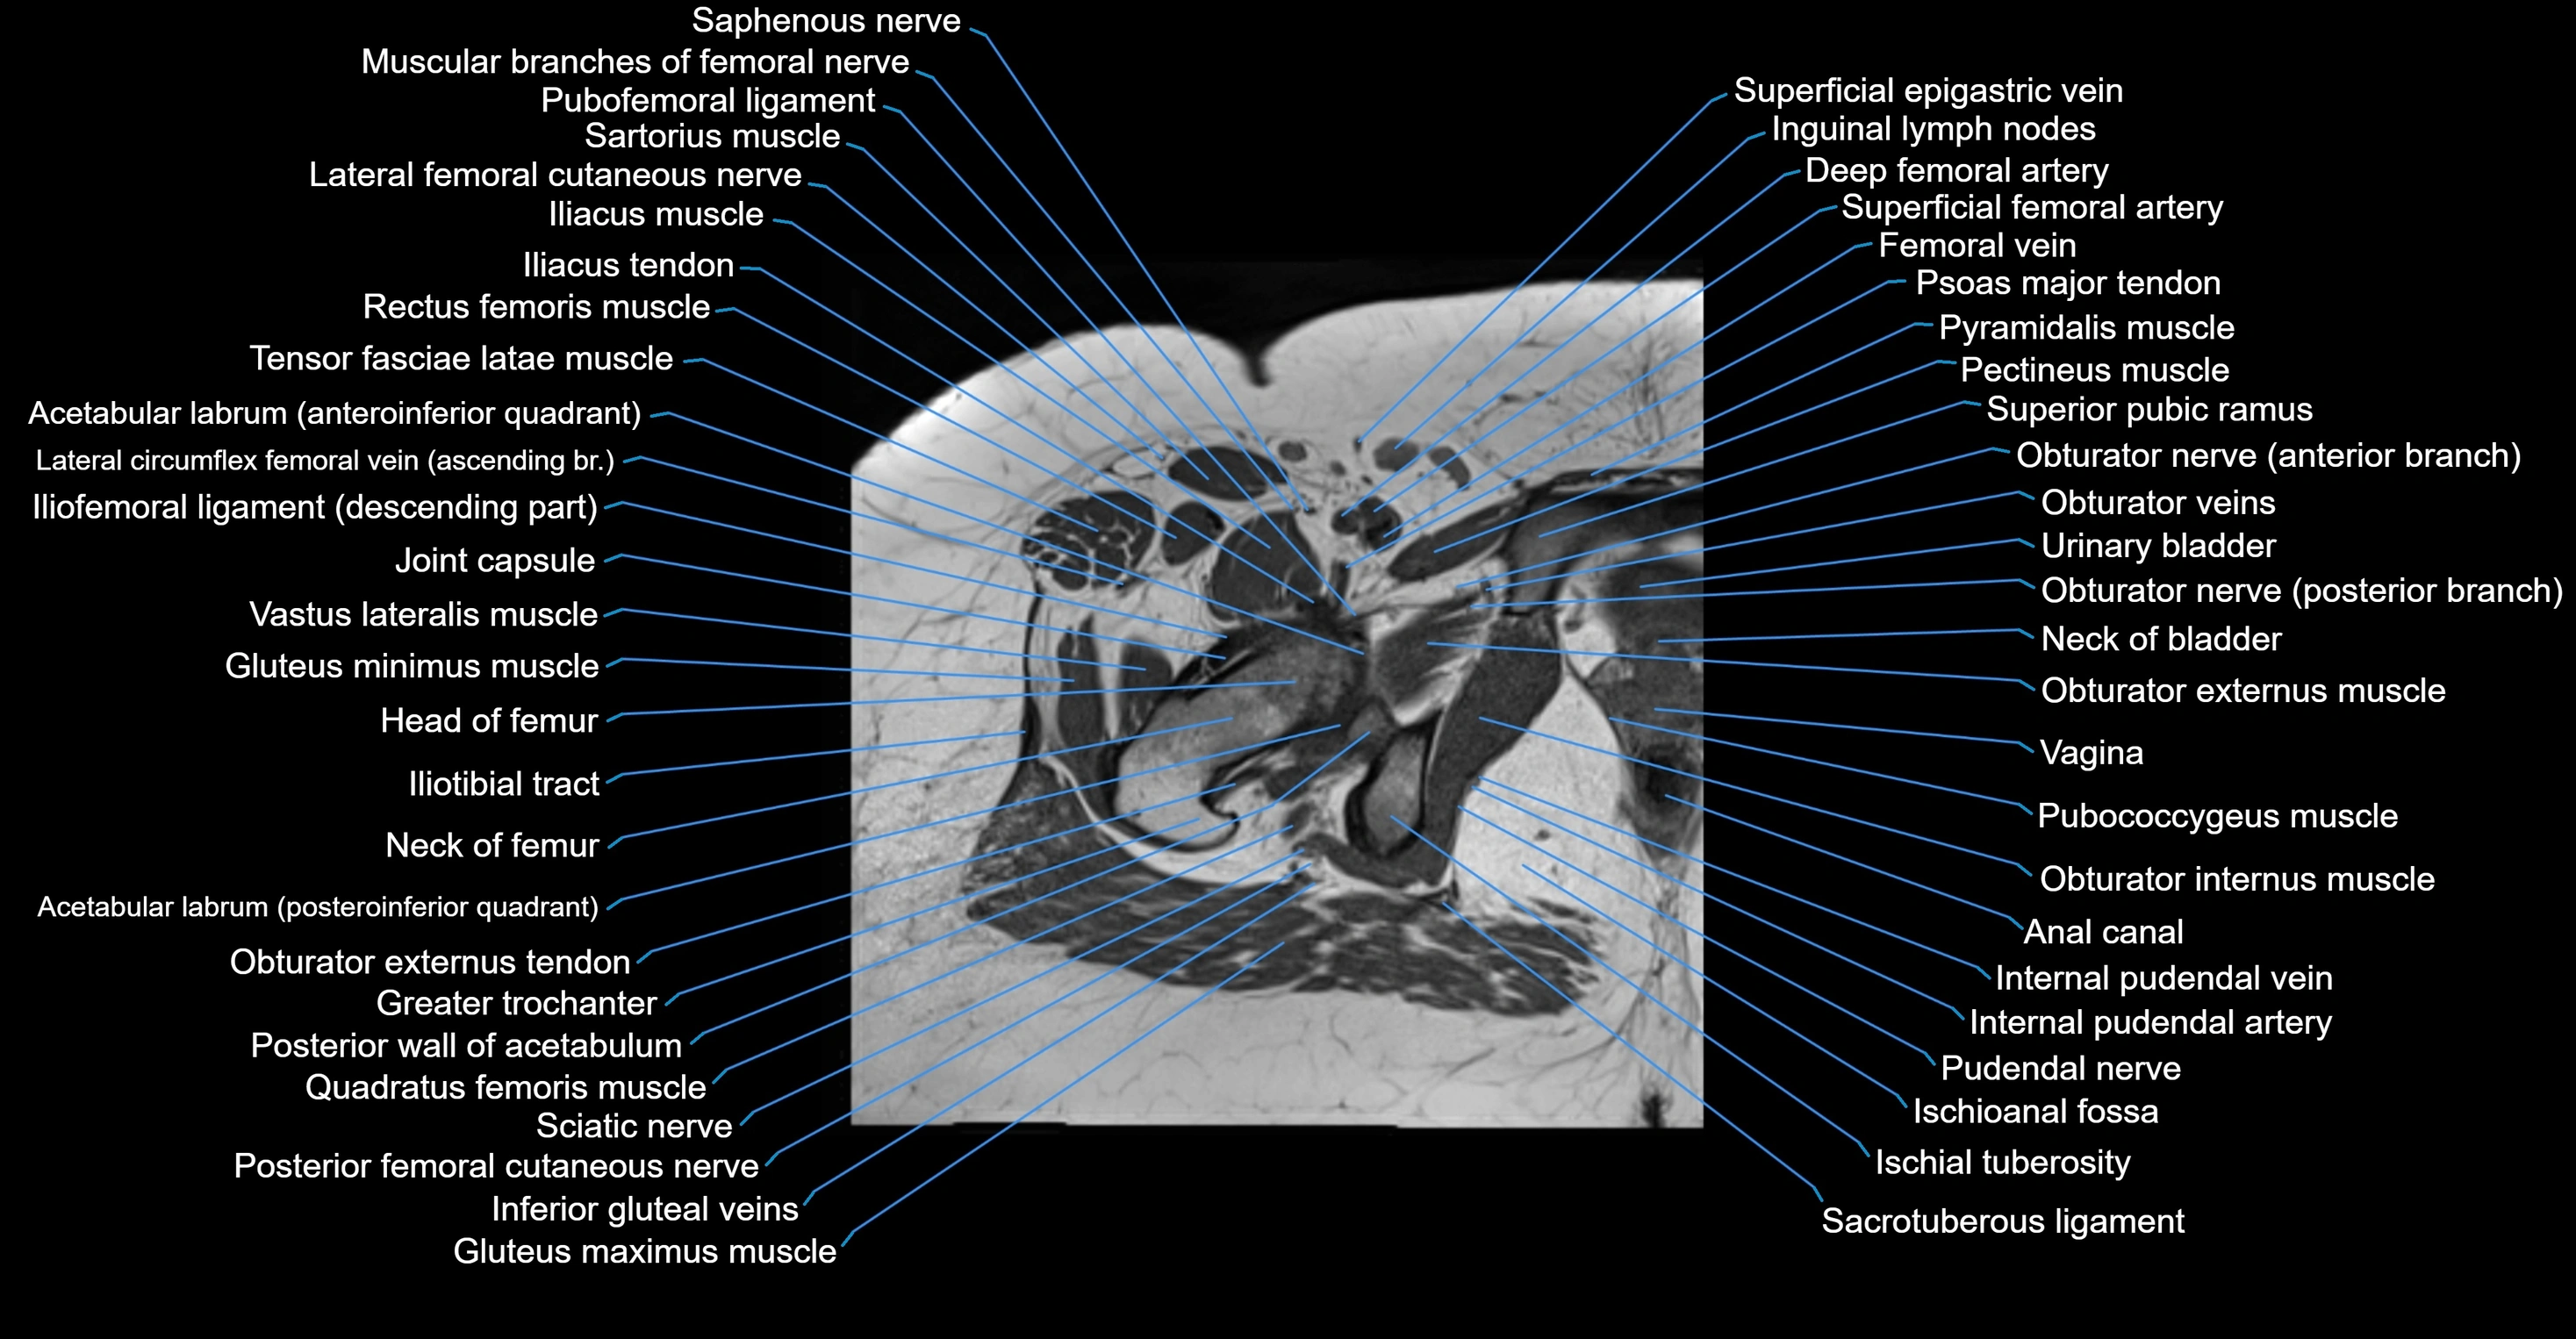

- Acetabular labrum

- Anal canal

- Head of femur

- Hip joint

- Iliopsoas tendon

- Iliotibial tract

- Neck of femur

- Obturator externus muscle

- Obturator internus muscle

- Pubococcygeus muscle

- Pubofemoral ligament

- Pudendal nerve

- Quadratus femoris muscle

- Sacrotuberous ligament

- Urinary bladder

- Vagina